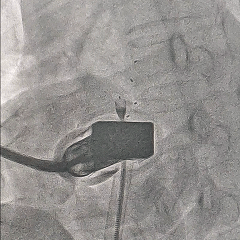

封堵器释放

5个显影点排列聚拢

超声四腔心切面下可见封堵器稳定夹持在房间隔两侧,盘面贴合,形态良好